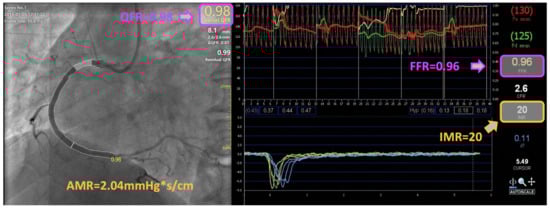

| FFR | 0.91 (0.87, 0.96) |

| QFR | 0.94 (0.91, 0.97) |

| IMR | 23.6 ± 6.8 |

| AMR, mmHg*s/cm | 2.5 ± 0.5 |